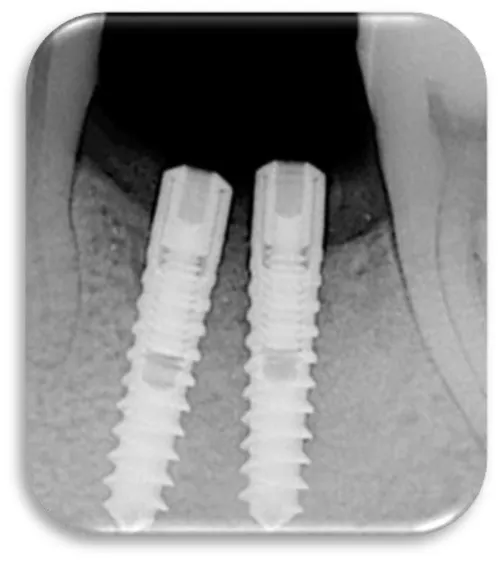

Woman at aged 37 year age, in good health condition and without any systemic diseases, allergic to penicillin came for prosthetic rehabilitation. She was without second premolar and first molar in the lower right quadrant. The patient was provided with dental implants at 45 and 46 (Figures 17-19). After a month on a 45-implant, retrograde peri-implantitis appeared. In chronological order, X-ray images are shown on figures from 17 to 20.

Different treatment strategies were performed in order to remove peri-implantitis. Provided treatment include: debridement of bone tissue, use of bone grafts from known biocompatible grafting materials, i.e. BioOS, disinfection of the surface of the dental implant. After 12 months, another radiography record was made, where ceramic crowns over the implants were seen and there was no longer peri-implantitis (Figure 20) [19,20].